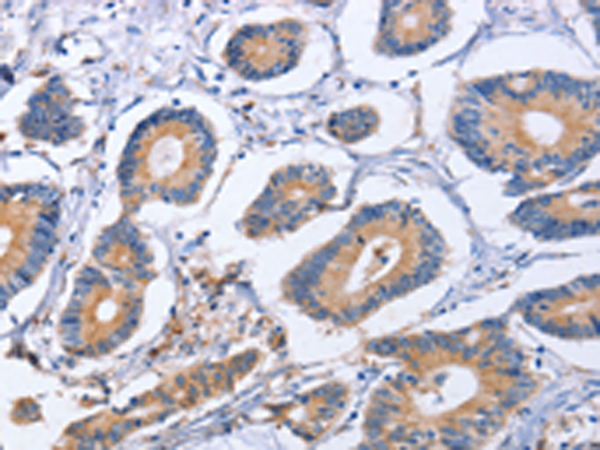

分类: 科研抗体货号: P07388别名:应用: IHC反应种属: Human, Mouse